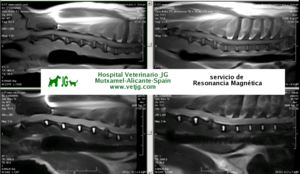

Síndromes neurológicos: cervicotorácico. Casos clínicos | |||||||||||||||||

Caso 2: |